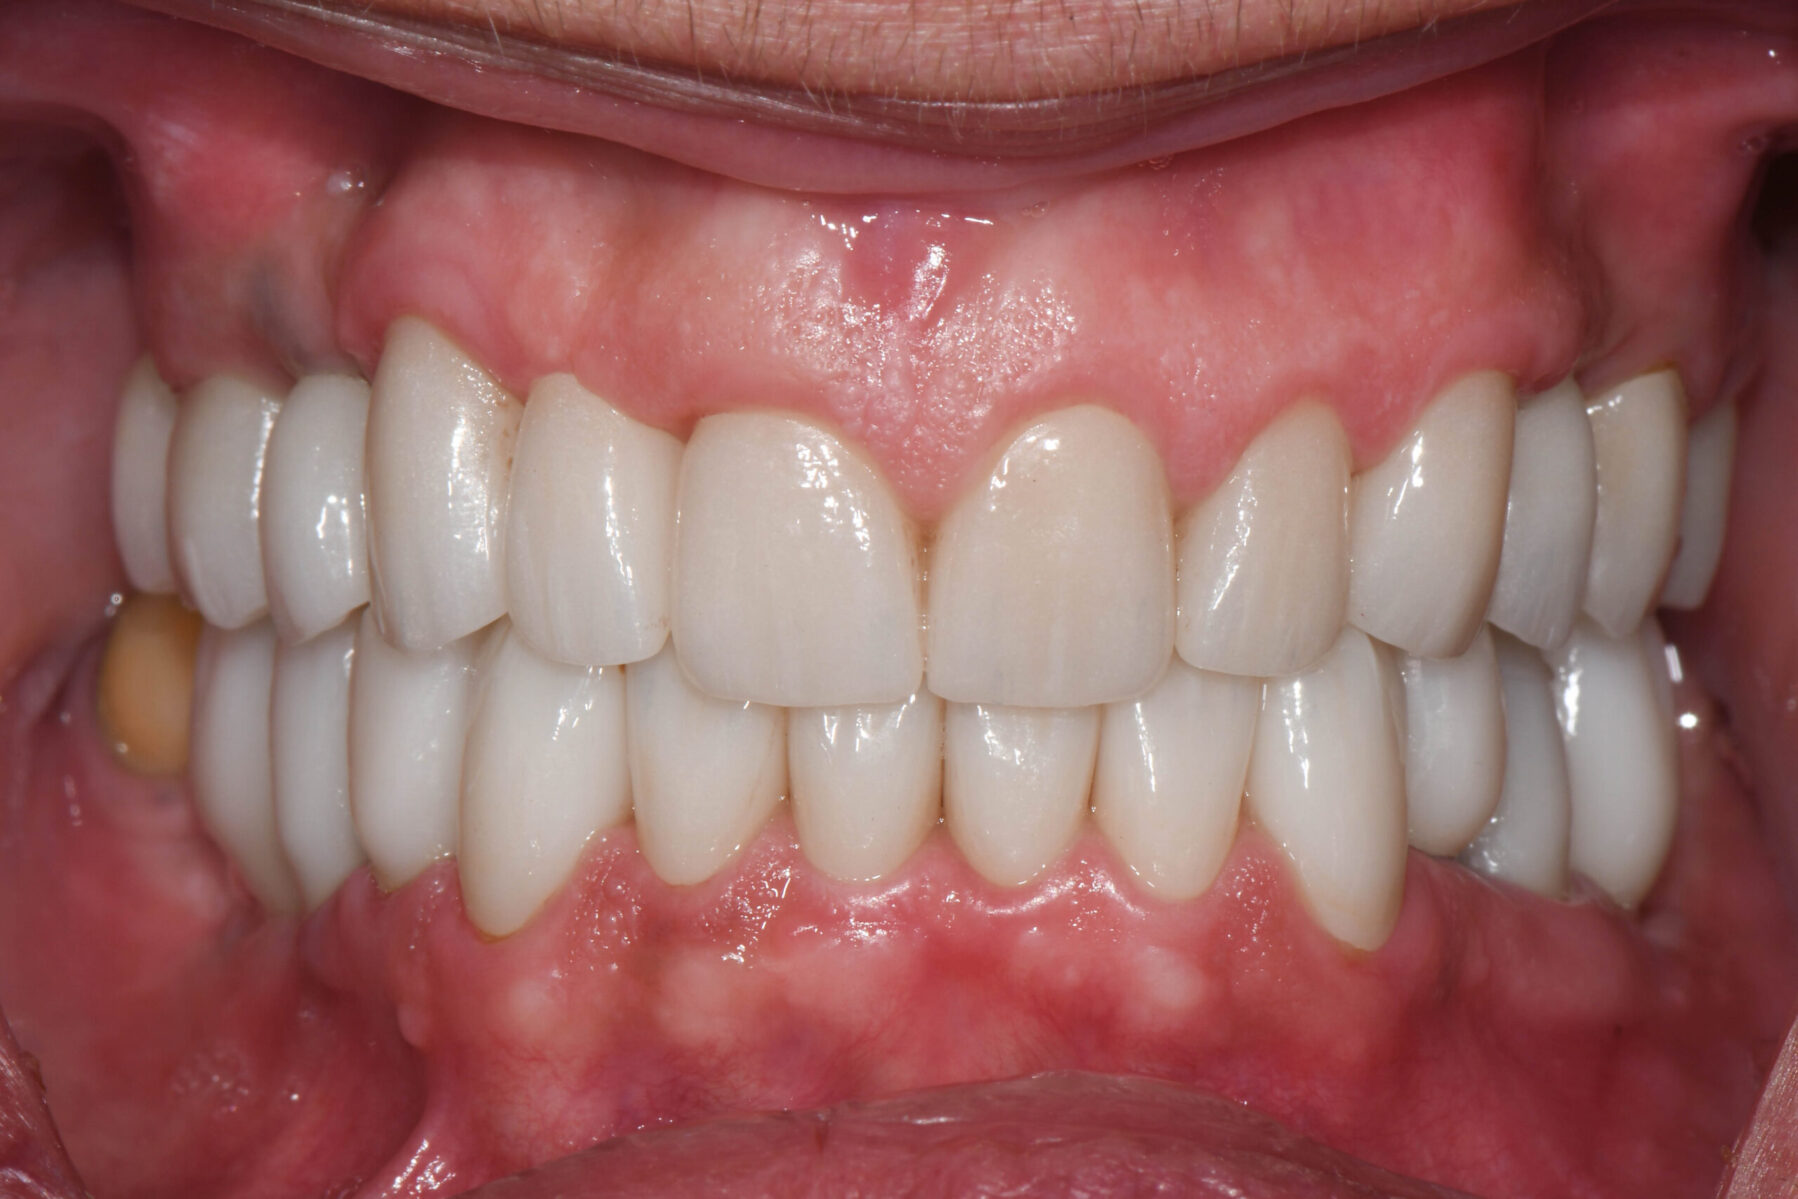

Full mouth rehabilitation encompasses a range of restorative dental procedures aimed at restoring the function, health, and esthetics of your entire mouth.

This may involve the use of crowns to protect and reinforce weakened teeth, dental implants to replace missing teeth, and veneers to improve the appearance of discolored or damaged teeth. Each treatment is tailored to match the color, shape, and size of your natural teeth, ensuring a cohesive and beautiful smile.

• Enhancing facial esthetics and boosting self-confidence

• Supporting optimal oral health and overall dental function